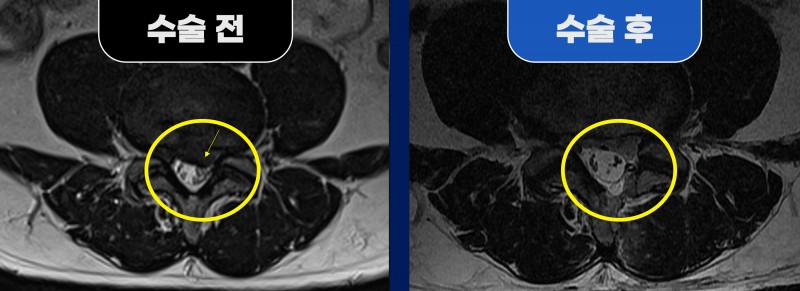

■ Before (수술 전) 38세 남성 환자분께서 심한 좌측 다리 방사통을 주소로 내원하셨습니다. MRI 검사 결과, 요추 4번 / 5번(L4/5) 부위에서 좌측 추간판 탈출증이 확인되었으며, 동시에 우측 추간공 협착증이 함께 동반된 상태였습니다. 문제는 디스크 제거 수술 시, 파열된 디스크 안쪽까지 과도하게 제거할 경우 오히려 우측 추간공 간격이 더 좁아질 수 있는 위험 요소가 있다는 점이었습니다. 하지만 환자분께서는 우측 다리 증상은 거의 없는 상태였기 때문에, 우측 구조물을 최대한 보존하면서 좌측 증상을 유발하는 디스크만 정확히 제거하는 양방향 내시경을 통한 좌측 추간판 제거술을 계획하게 되었습니다. ■ After (수술 후) 수술 중 좌측 신경은 파열된 디스크에 의해 심하게 눌려 부종과 충혈 소견이 확인되었습니다. 이에 해당 디스크 조각과 압박 원인을 제거하고 신경을 충분히 감압해 주었습니다. 수술 후 MRI에서는 파열된 추간판이 중앙에서 좌측까지 깨끗하게 제거된 모습이 확인되었으며, 특히 흥미로운 점은 수술 전 협착되어 있던 우측 추간공 공간이 자연스럽게 넓어진 변화가 관찰되었다는 점입니다. 이는 통증의 주요 원인이 제거되면서 과도하게 긴장되어 있던 척추 주변 근육의 긴장이 풀리고, 디스크 간격(높이)이 회복되면서 자연스러운 공간 복원이 이루어진 결과로 볼 수 있습니다. 환자분은 수술 후 좌측 다리 방사통이 현저히 감소하였고, 빠른 일상 복귀가 가능할 정도로 회복되었습니다. 청담해리슨송도병원은 단순히 병변만 제거하는 치료가 아닌, 척추 전체의 균형과 기능 회복까지 고려한 정밀 내시경 수술을 통해 환자의 회복 속도와 치료 결과를 함께 높이고 있습니다. |